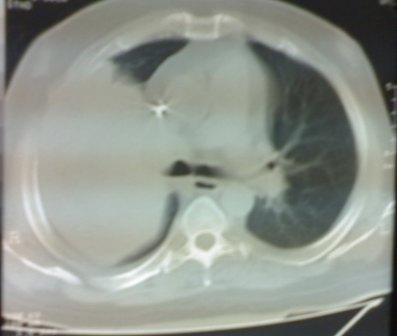

This photo is for a patient, with

chronic renal failure and on regular hemodialysis, presented with fever

and constitutional symptoms.

The well-circumscribed pattern of the lesion encouraged us to try

aspiration that revealed frank pus, so the first impression was with the

diagnosis of encysted empyema, particularly that our patient is with

chronic failure and on disalysis.

But if you meticulously re-check the photo especially the plain X-ray;

you can see an area of increased density adjacent to the trachea that

may reflect an underlying mass, so bronchoscopy was done to reveal a

mass at the right upper bronchus.

The histopathological examination of the obtained biopsies revealed

"sqaumous cell carcinoma".